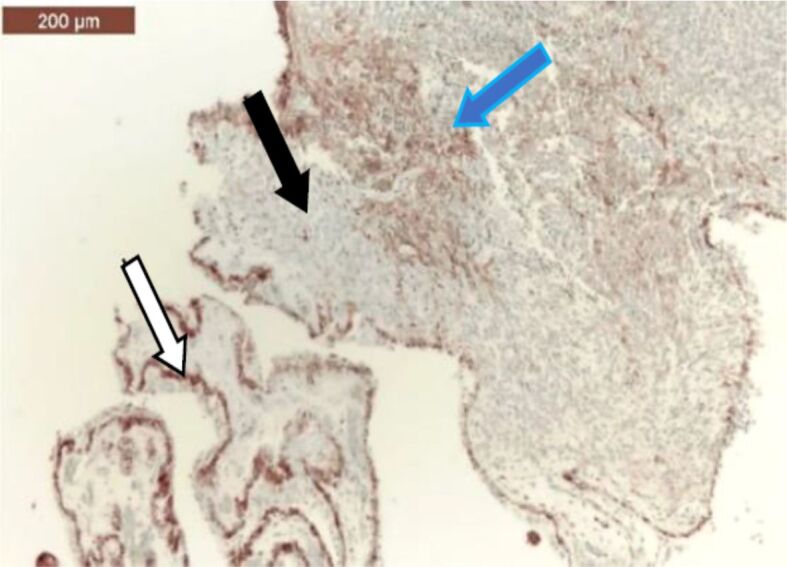

Ocular melanoma is a rare but complex disease in current medical practice. Our retrospective study spans over a period of 28 years and analyzed uveal and conjunctival melanomas that were consecutively admitted, diagnosed, and treated in the 2nd Ophthalmology Clinic of Prof. Dr. Nicolae Oblu Emergency Clinical Hospital, Iaşi, Romania. The patients were selected from the records of the Department of Pathology of our Hospital, being diagnosed by standard histopathological techniques. The aim of this study was to summarize the epidemiological and pathological aspects of uveal and conjunctival melanomas in Northeastern region of Romania. In our study, we did not notice a predilection of uveal and conjunctival melanoma to one particular gender. The most common histological subtypes of ocular melanomas were the heavily pigmented spindle cell subtype, followed by the epithelioid subtype. Our patients sought medical help in a timely manner, before the systemic invasion of the disease could develop.

Abstract Image